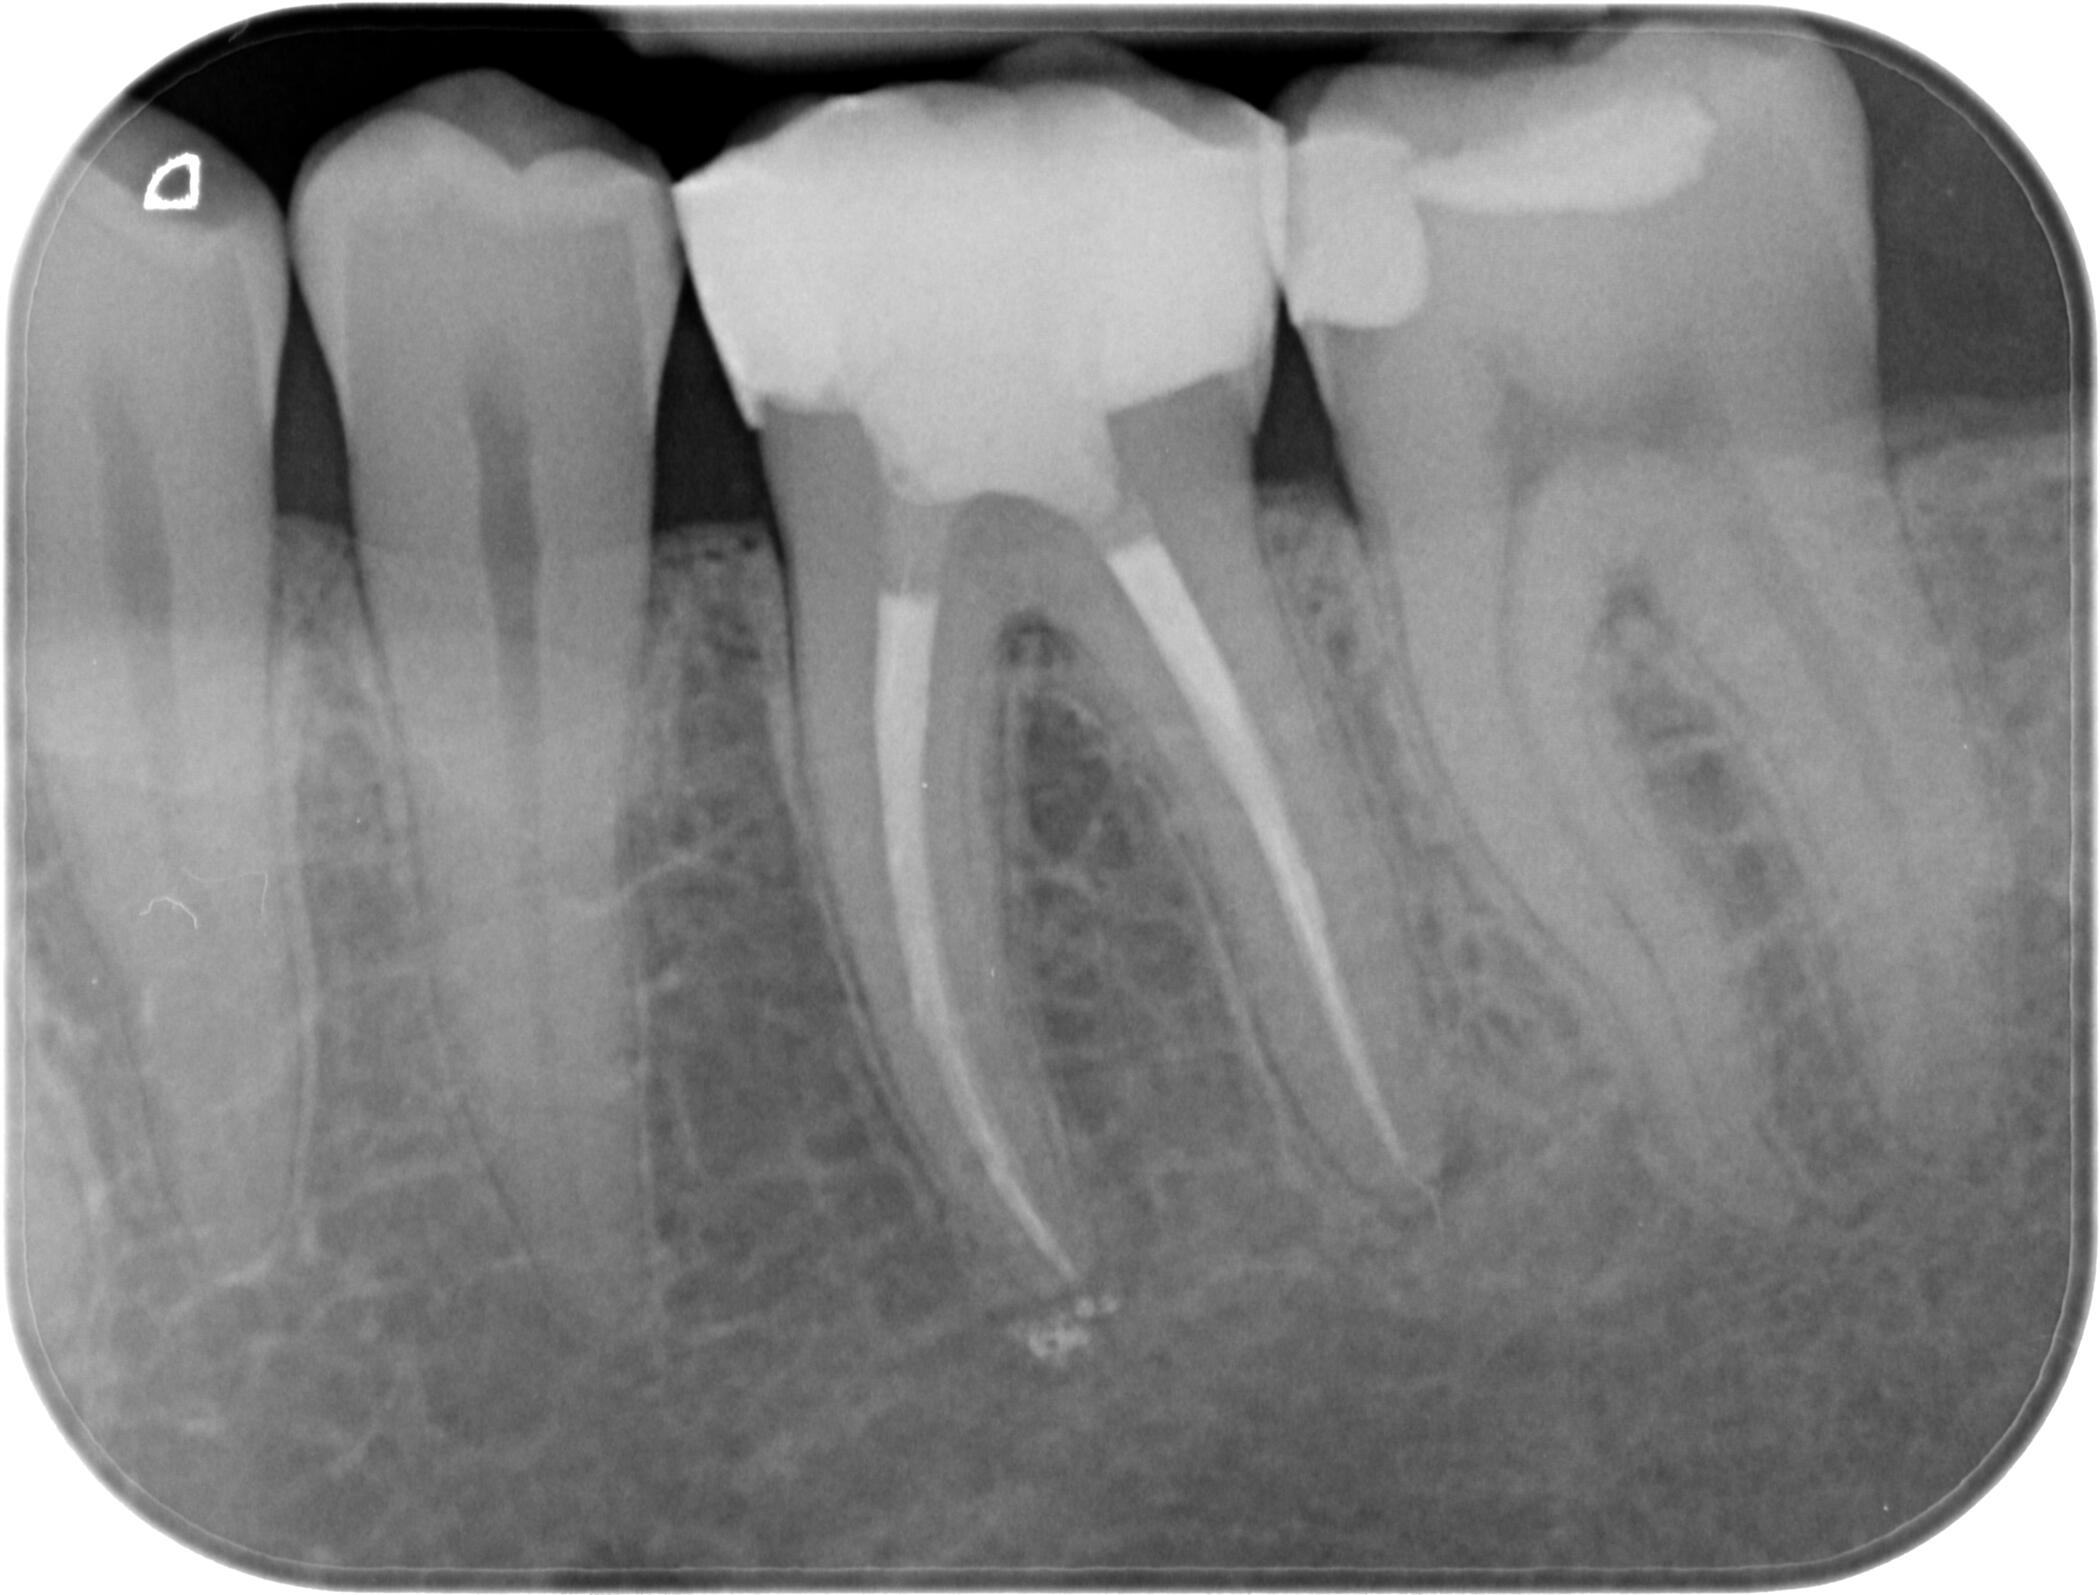

Периапикална / Сегментна рентгенография

Planmeca ProX

Интраорален рентгенов апарат, характеризиращ се с бързо и лесно позициониране при изследване, за максимален комфорт на пациента.

За още по-голяма безопасност на пациентите, интраоралният ни рентген е оборудван и със специален тубус, който фокусира рентгеновите лъчи само в мястото, което искаме да бъде диагностицирано!

Dürr VistaScan

VistaScan е дигитален скенер за интраорални фосфорни плаки. Те са:

- с висока разделителна способност.

- меки и гъвкави, наподобяващи конвенционалните рентгенови плаки.

- обработват се за няколко секунди.